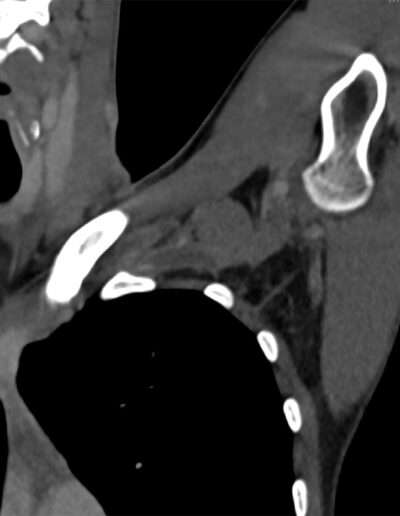

SHOULDER CASE SUMMARY:

| Shoulder | Left |

| Patient | 27 y/o, Female, right-handed |

| Profession/Sport | Gym manager / Body building |

| History | Painful shoulder and biceps |